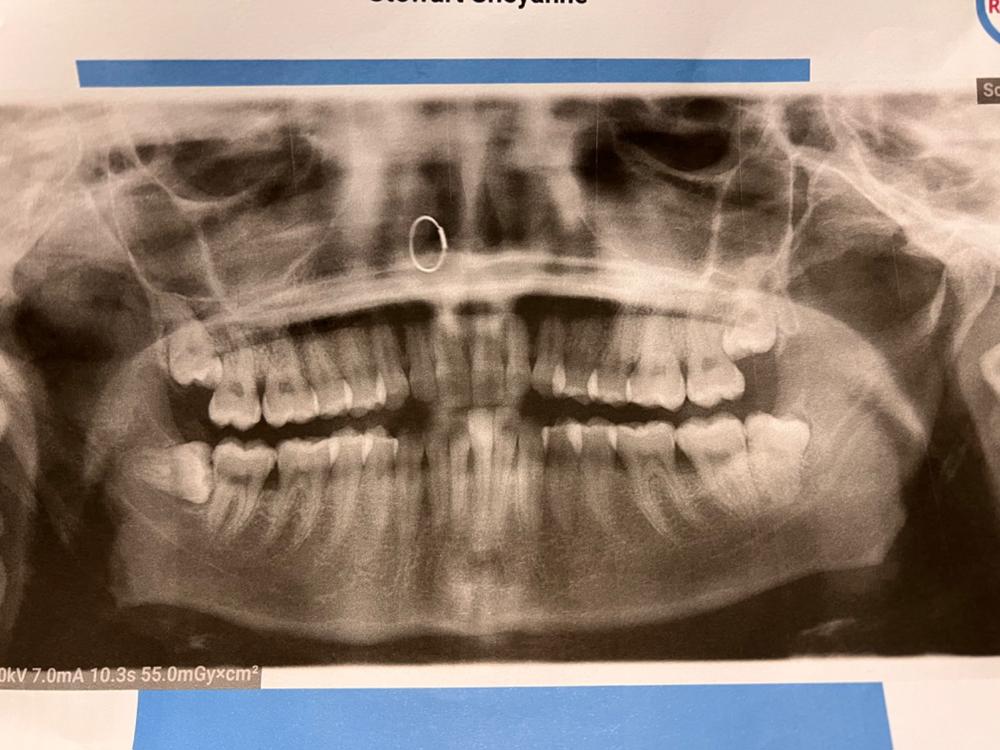

I am in need of getting my wisdom teeth removed asap, I am in pain a lot and have a mild infection on one side. One of my wisdom teeth is growing in sideways and the other has been leaking fluid into my mouth most days. It’s extremely unpleasant and I’m unable to afford the surgery on my own funds especially after an emergency vet bill of $1480 yesterday for our cat. I use mouth wash and salt water rinses to get by but there’s only so much that can do.

For surgery to remove 2 wisdom teeth under full sedation and any extra dental care needed at the time